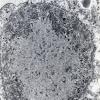

SSPE (2)